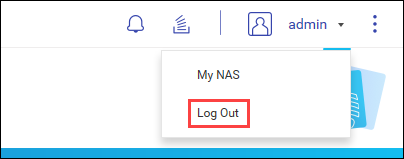

应用实体 (AE) 管理

在 DICOM 中,应用实体 (AE) 表示 DICOM 网络中的端点系统或程序,例如设备或 PACS 服务器。将 NAS 配置为 PACS 服务器时,将它视为一种 AE。

在 MediQPACS 的“AE Management”(AE 管理)屏幕中,用户可以在本地或外部网络上添加、编辑、删除、搜索和测试其他 AE 的连接。

单击  以查看“AE Management”(AE 管理)屏幕。

以查看“AE Management”(AE 管理)屏幕。